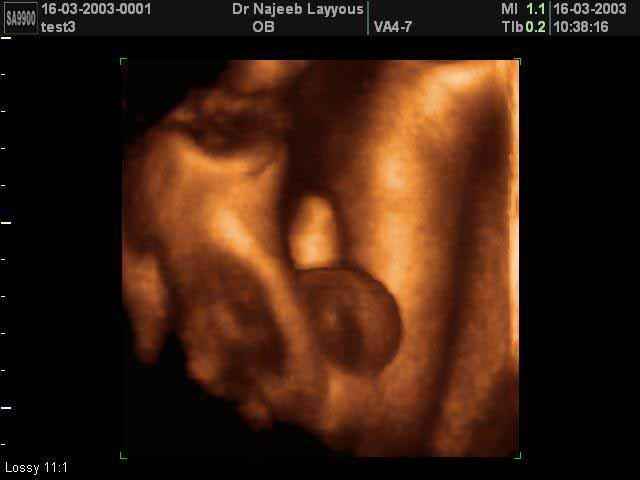

- Fetal Face Ultrasound Photos